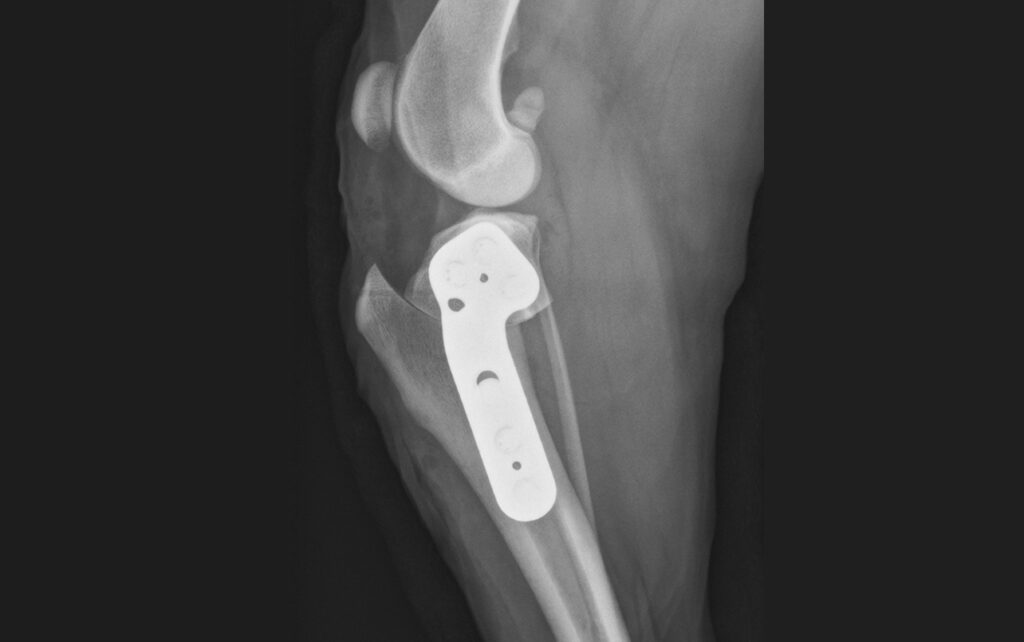

With canine TPLO surgery, the surgeon alters the angle of your dog’s tibia (the shin bone) so that the knee can still stabilize and function without depending on the torn ligament. In brief:

- An incision is made and opened near the knee

- The tibial plateau is cut and rotated to the right angle.

- A metal plate and screws are used to hold it in place.

- The incision is closed and bandaged.

The procedure typically lasts about two hours. Afterward, your dog is closely monitored as they recover from anesthesia.